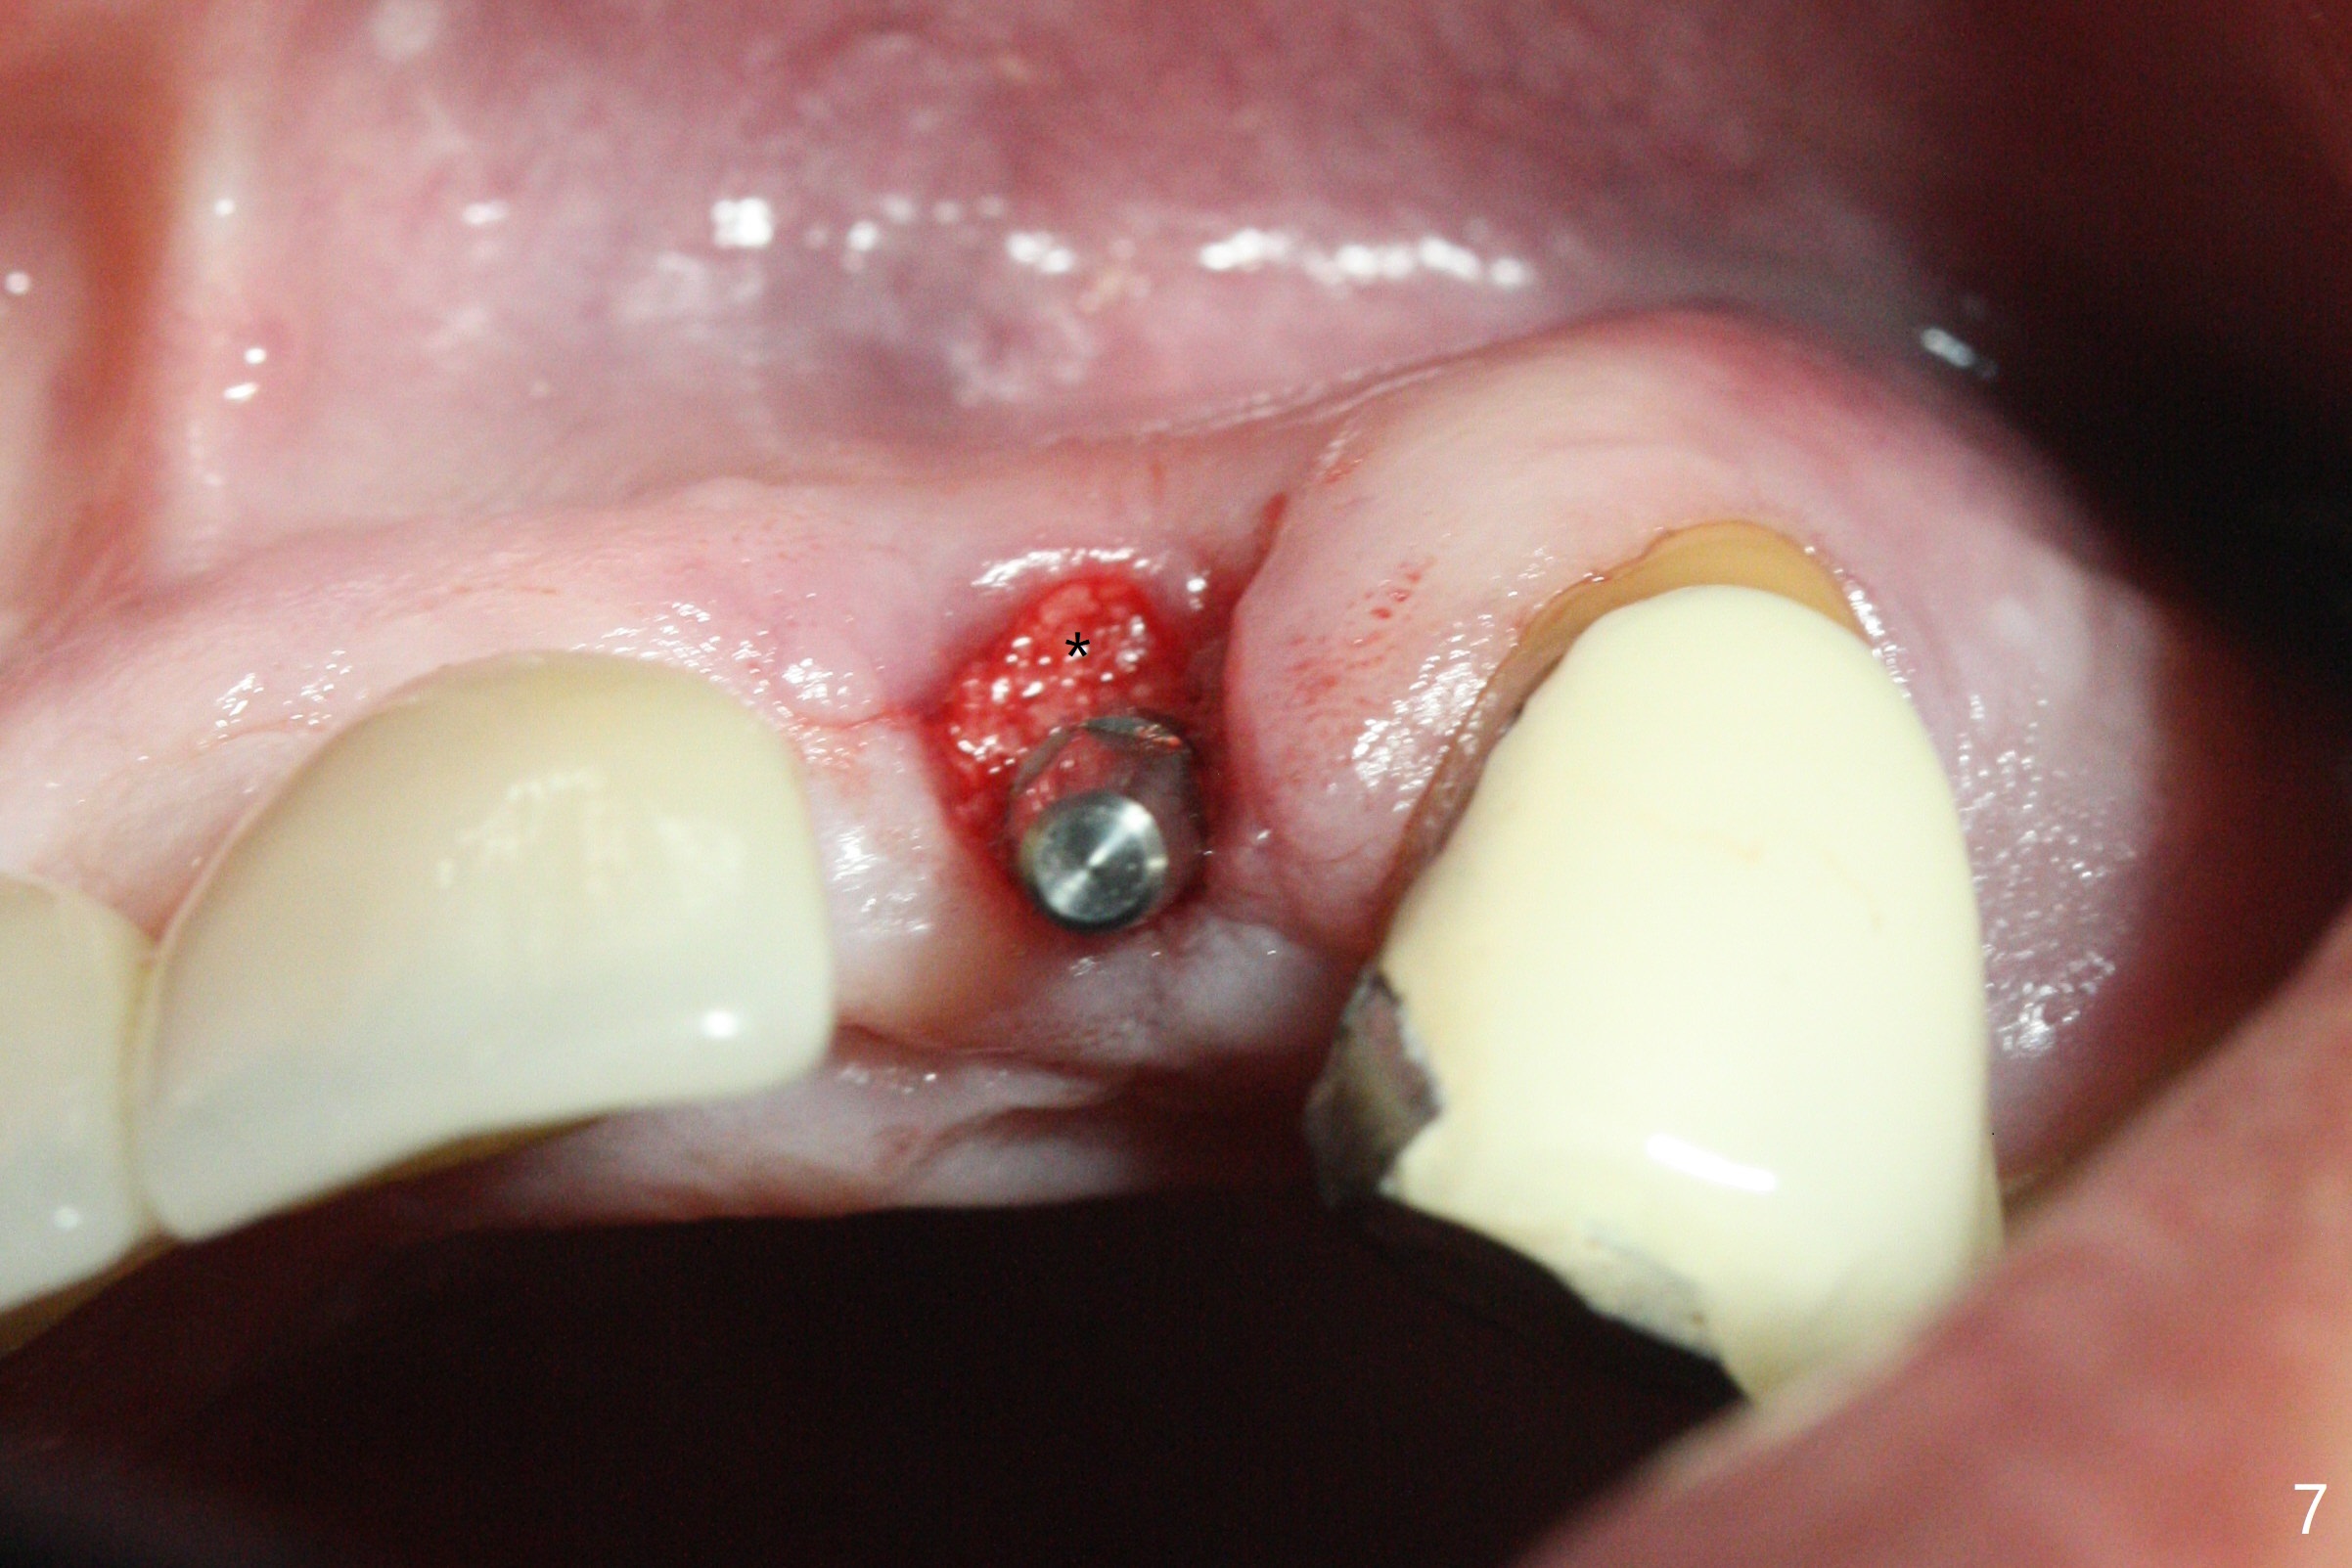

The tooth #10 has severe gingival recession (Fig.1) with loss of the buccal plate (Fig.2 *). After the initial osteotomy depth (Fig.3) increases by 2 mm, a 2.5x14(2) mm 1-piece implant is placed with insertion torque >60 Ncm (Fig.4). Palpation indicates the native bone apparently wider than CT shows. There is no sign of buccal or palatal plate perforation by palpation during osteotomy or implant placement. Vera Graft is placed repeatedly around the coronal threads (Fig.5-7 *). An immediate provisional is fabricated to close the socket (Fig.8). The buccal plate appears to collapse 1 month postop (cortical plate graft apparently more appropriate in this case); the margin of the provisional is trimmed so that the gingiva may grow incisally (Fig.9). The provisional dislodges several times postop due to short abutment. By nearly 4 months postop, the coronal bony defect seems to have been repaired (Fig.10 *). The tooth #11 has tenderness with bone loss (Fig.10 ^), corroborated by CT (distal bone loss, Fig.11 *). Since the apical bone is narrow (Fig.12), a narrow long implant is expected (Fig.13). Use an implant (3.5x13 mm) consistent with those at #14 and 15.